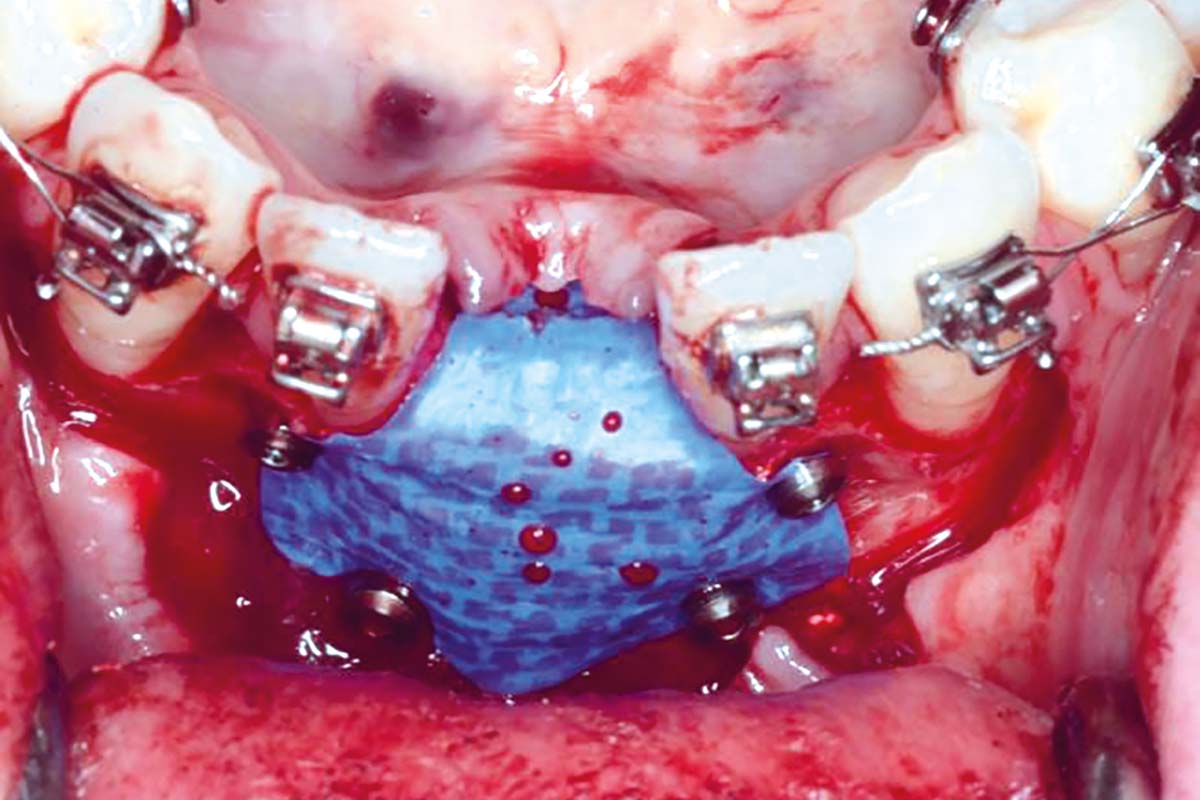

Regenerative corticotomy to compensate lower incisor malocclusion with cerabone® and mucoderm®

Initial view of the clinical case: Class III malocclusion

Treatment plan: Regenerative corticotomy (PAOO)